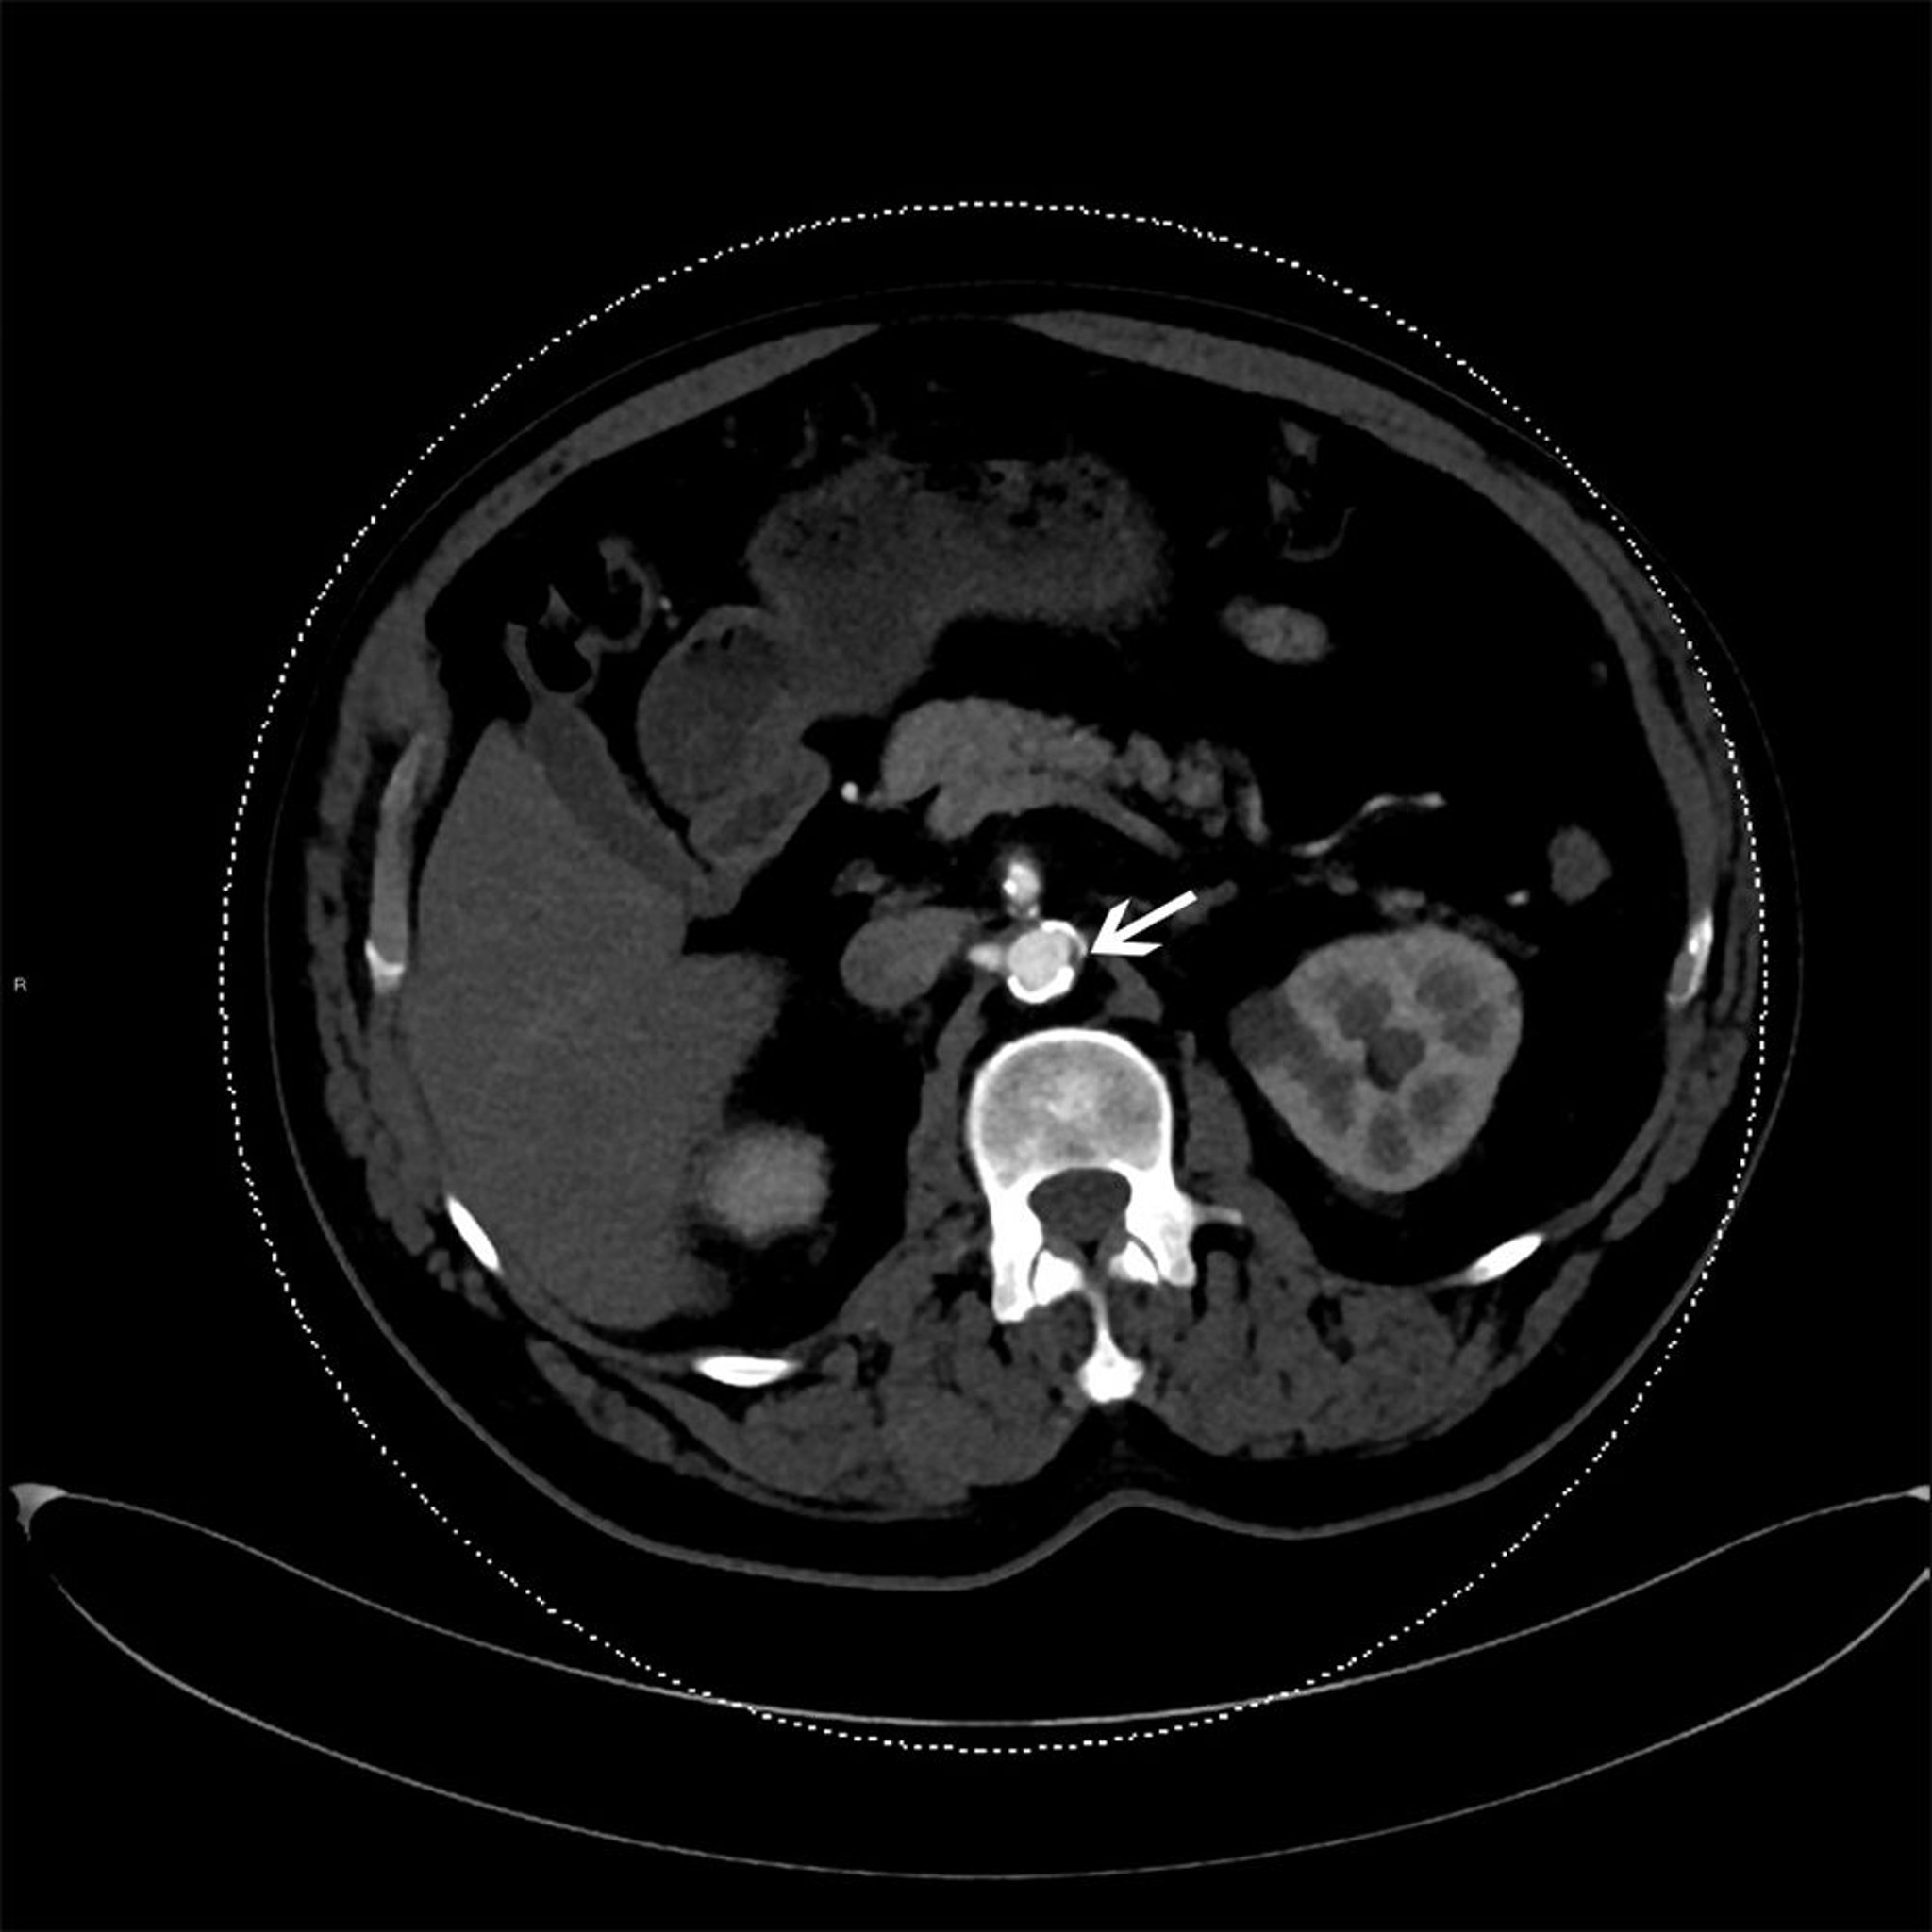

• Noncontrast CT, including coronary artery calcium scoring CT: CT is used to evaluate the presence and extent of calcified plaques. It can be used as a dedicated examination (eg, coronary calcium scoring CT with standard ECG-gated image acquisition) or for opportunistic evaluation using CT images acquired for other indications.

• CT angiography (CTA): CTA uses iodinated contrast-enhanced CT to evaluate atherosclerotic plaque morphology and detect stenosis severity with high spatial resolution. This technique involves ionizing radiation and can be applied to any vascular bed, making it ideal for small, mobile vascular beds like the coronary arteries.

Calcium scoring CT uses ECG-gated noncontrast CT to quantify calcified atherosclerotic plaque burden and can be used for risk stratification and reclassification, to help make decisions about withholding or recommending statin therapy. For example, in patients with intermediate risk (estimated 10-year ASCVD risk ≥ 7.5% but < 20%) or in selected patients with borderline risk (estimated 10-year ASCVD risk ≥ 5% but < 7.5%), if the calcium score is zero, it is reasonable to withhold statin therapy and reassess in 5 to 10 years as long as the patient does not smoke, does not have diabetes, and has no family history of premature coronary artery disease; if the calcium score is ≥ 100, it is reasonable to initiate statin therapy. A calcium score of zero has an excellent negative prognostic value, with an estimated 1% risk for major adverse cardiovascular events over 10 years (11, 12).